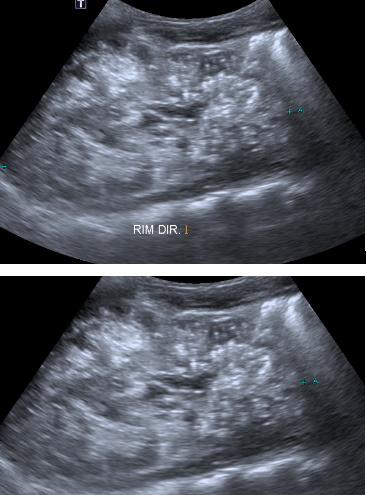

Lactente de um ano, sexo masculino, sem diagnóstico definitivo, realizou ultrassonografia de vias urinárias para avaliação de “rins aumentados” observado na ultrassonografia obstétrica, sem seguimento posterior. Paciente em acompanhamento recente com nefrologia, evoluindo com piora da função renal.

Diante dos achados de imagem, qual sua hipótese diagnóstica?

BDoença policística autossômica recessiva